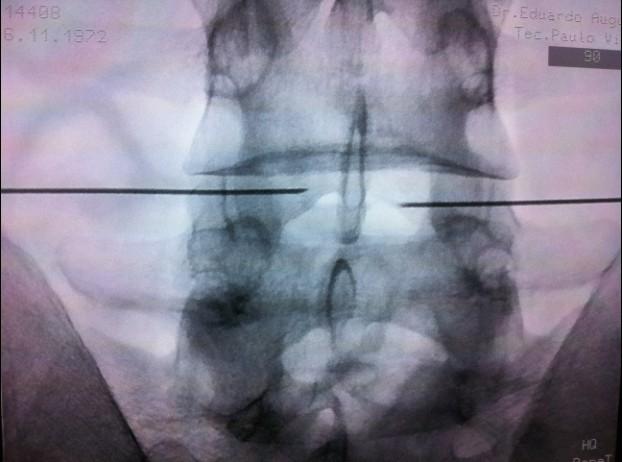

Durante a Nucleoplastia, o paciente é posicionado de forma adequada e é administrada anestesia local ou sedação consciente. Um dispositivo especializado, chamado de Núcleo Coblation, é inserido no disco intervertebral afetado, com auxílio de guias de imagem, como fluoroscopia.

Ao lado, exemplo de IDET com acesso bilateral.